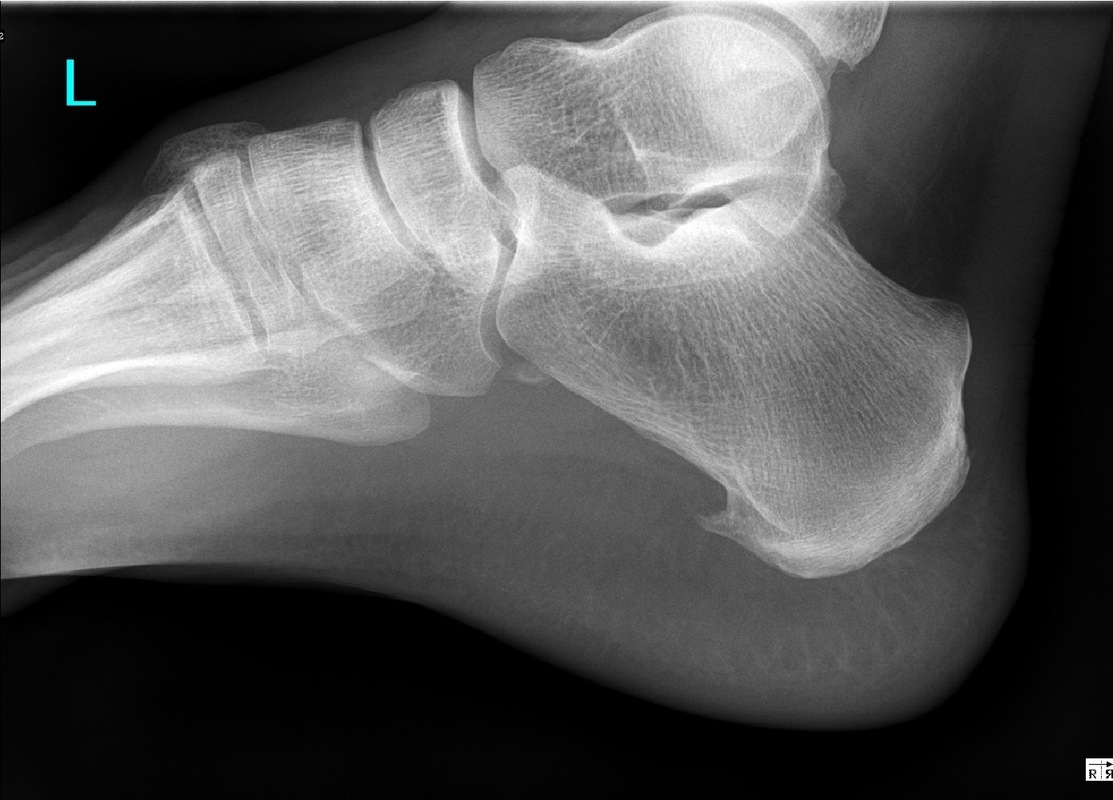

Charakteristika deformity: Haglundova pata vzniká nejčastěji trvalým tlakem obuvi v místech, kde je kost kryta pouze kůží se slabou vrstvou podkoží. Dochází zde ke dráždění okostice, která se tomuto tlaku brání nadprodukcí kostní tkáně.